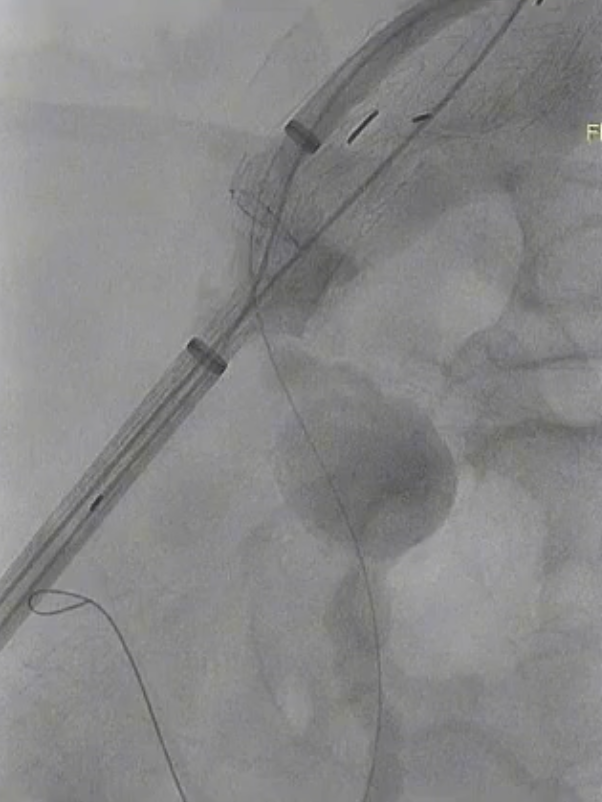

术前情况:78岁男性,腹主动脉瘤和髂动脉瘤,同时右髂总动脉近端、远端严重狭窄且近端扭曲,左髂总动脉近端、远端狭窄,髂内开口狭窄。

手术过程:采用短主体翻山技术重建右侧,在输送主体前,针对髂动脉多处狭窄、扭曲的情况,使用球囊预扩。之后,在微导丝、微导管的配合下艰难超选髂内动脉,成功将支架置入。

术后情况:造影显示患者髂内动脉血流恢复正常,手术达到预期效果。